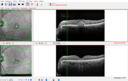

Most viewed - Collapsed Vitelliform Pattern Dystrophy

74 year old female: Seeing "Diamonds in central vision" when first waking up OU. Duration of Problem: about 6 weeks. Location: central vision. Modifying Factors: Lasts just a few minutes. Medical Hx: Cancer (Breast). Surgical Hx: Lumpectomy. Appendectomy. nose surgery. Systemic Meds: Ibrance. Faslodex. Zomita. Vitamin D3. VA OD: Dsc20/40+2 VA OS: Dsc20/50+1 IOP: TP: OD:18 OS:21

Pattern Dystrophy with Collapsed Vitelliform117 views74 year old female with vision loss in eye with collapsed vitelliform lesion.